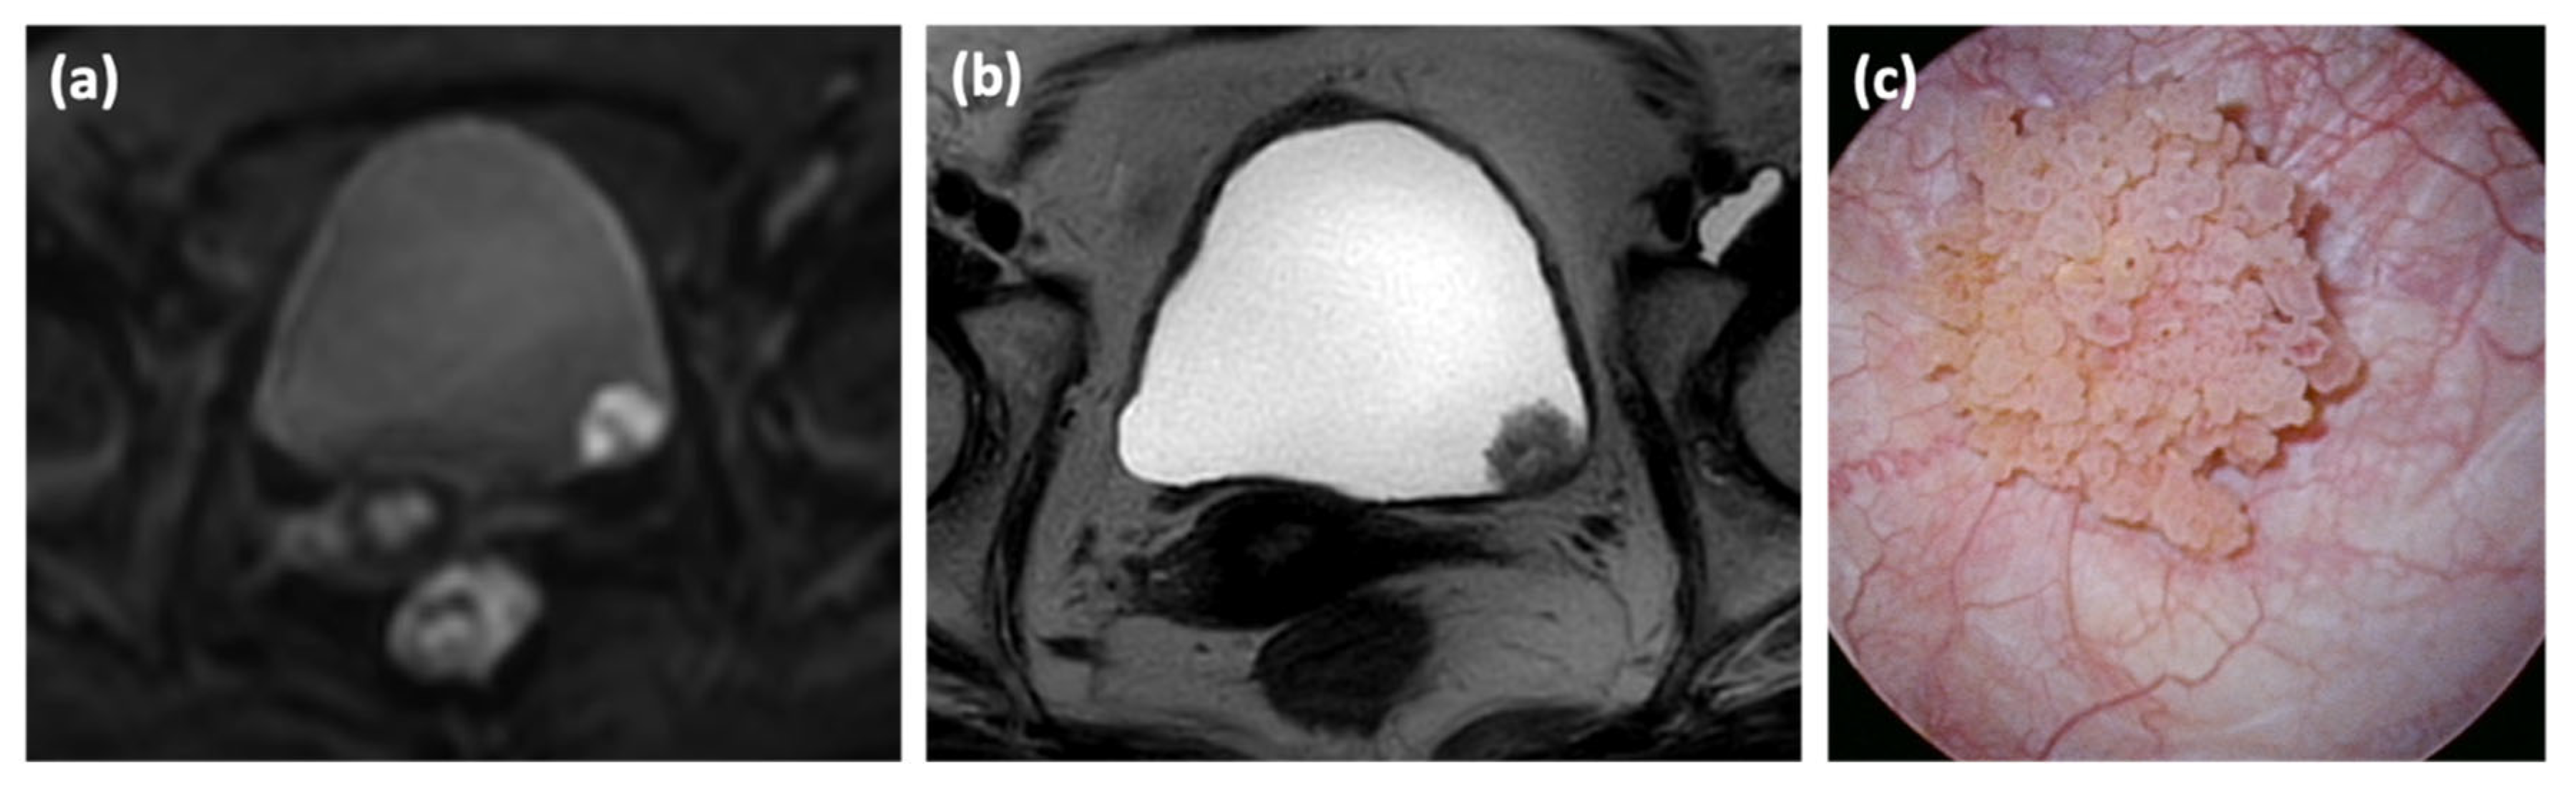

2.2. Image Analysis

- Yajima, S.; Yoshida, S.; Takahara, T.; Arita, Y.; Tanaka, H.; Waseda, Y.; Yokoyama, M.; Ishioka, J.; Matsuoka, Y.; Saito, K.; et al. Usefulness of the inchworm sign on DWI for predicting pT1 bladder cancer progression. Eur. Radiol. 2019, 29, 3881–3888. [Google Scholar] [CrossRef]